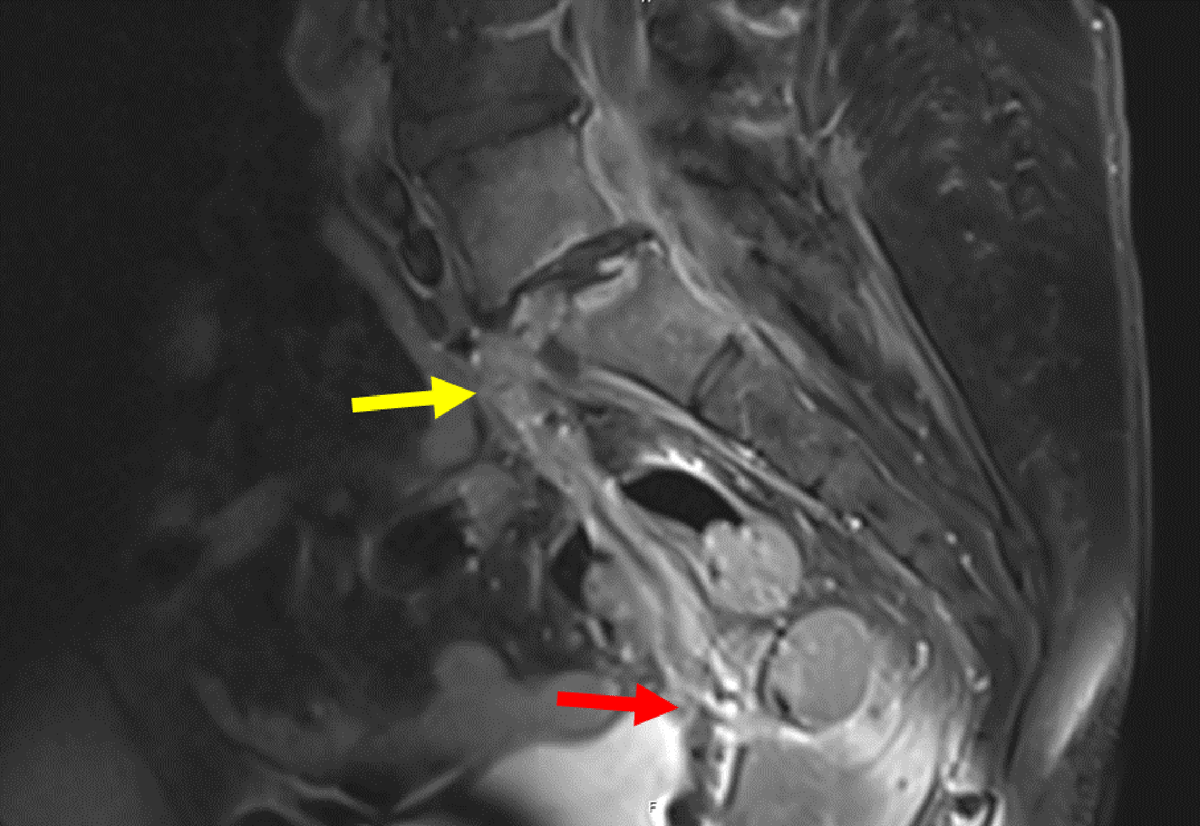

Figure 10

Sagittal contrast MRI in T1 weighting: Pre-operative MRI showing an epidural collection behind the vertebral body of L5 and within the L5-S1 disk (yellow arrow), fistulising into the vagina (red arrow).